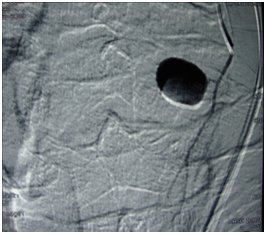

A 62-year-old man was admitted in our Otolaryngology Department of presenting sore throat, disphagia and mild dyspnea after a transesophageal ecocardiography guided cardioversion performed 3 days before. The endoscopic examination of upper aereodigestive tract showed a diffuse soft edema of arytenoids and pharyngolaryngeal tract without airway obstruction. A corticosteroid therapy was started and the symptoms quickly improved but two days later the patient presented suddenly a hemorrhage from the superior aereodigestive tract. The endoscopic examination revealed a swelling of the left lateral wall of the hypopharynx and a hemorrhage from the apex of the swelling witch stopped spontaneous after few minutes. A CT scan of neck revealed an active arterial bleeding with pseudoaneurysmal dilatation of 1,2cm of diameter arising from a fine branch of external carotid artery and a well defined homogeneously enhancing mass, 9.5 x 3.2cm diameter in left neck spaces extending superiorly to parapharyngeal spaces, inferiorly to hypopharynx displacing hyoid bone, thyroid cartilage, posterior to crycoid cartilage displacing cervical esophagus and laterally to subcutaneous tissue displacing sternocleidomastoid muscle (Figure 1). The mass was suggestive for hematoma. The angiography revealed a pseudoaneurysm with active bleeding of the terminal tract of superior thyroid artery (STA) (Figure 2). An endovascular procedure was performed with a superselctive microcateter and a endovascular occlusion by coil embolizzation of STA with exclusion of the pseudoaneurysm demonstrated at the end of the procedure (Figure 3). The symptoms resolved after one day from the endovascular procedure. The patient was discharged after two days without evidence of bleeding and an endoscopic control after 4 weeks revealed a disappearance of swelling.

Figure 3 Angiography illustrating endovascular occlusion by coil embolization.